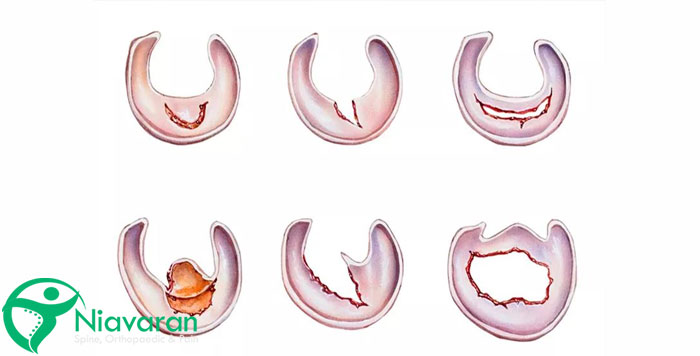

پارگی مینیسک پا ممکن است به شکلهای مختلفی اتفاق بیفتد. پزشکان متخصص، صدمات وارده به این بخش از زانو را در 6 نوع مختلف معرفی میکنند که در ادامه، هر کدام را توضیح میدهیم:

پارگی شعاعی مینیسک زانو

شاید شما هم بدانید که این مدل از پارگی مینیسک زانو چیست؛ چون اکثر افرادی که آن را تجربه میکنند، جزو این مدل هستند. این نوع پارگی، بیشتر در ناحیه سفید زانو و در جایی که خون وجود ندارد، اتفاق میافتد. به همین دلیل اغلب به صورت خود به خود ترمیم نمیشود. بنابراین دکتر فوق تخصص زانو با جراحی، بخش آسیبدیده زانو را حذف میکند.

پارگی ناکامل مینیسک

نام دیگر این نوع بیماری، پارگی درون مینیسک است و بیشتر بر اثر ساییدگی زانو اتفاق میافتد؛ به همین دلیل با گذشت زمان، میزان درد زانو برای چنین افرادی بیشتر میشود. همچنین اغلب این پارگیها، نشانهای برای بیماری های دژنراتیو اولیه مینیسک است.

پارگی افقی مینیسک زانو

پارگی افقی مینیسک زانو، در امتداد منحنی مینیسک قرار دارد. به این صورت که در قسمتهای عروق خونی یا در مرکز مینیسک، پارگی ایجاد میشود که هر کدام روش درمان خاصی دارند. اگر پارگی افقی در قسمت عروقی و خونی باشد، نیازی به برداشتن قسمت آسیبدیده مینیسک وجود ندارد و امکان ترمیم آن به آسانی وجود دارد. اما اگر پارگی افقی در مرکز مینیسک ایجاد شود، امکان بهبود آن حتی با جراحی هم غیر ممکن است.

پارگی فلپ مینیسک پا

پارگی فلپ، یکی از غیر معمولیترین و خاصترین انواع پارگیها است که بر اساس آن، بخشی از غضروف پوست کنده میشود. این اتفاق باعث قفل شدن زانو یا گرفتگی آن میشود. برای درمان این آسیب، جراح مقدار بسیار کوچکی از مینیسک را خارج میکند.

پارگی پیچیده مینیسک زانو

پارگی پیچیده مینیسک، در واقع ترکیبی از چند مدل پارگی مانند پارگی شعاعی و افقی است. بنابراین با وجود پارگیهای مختلف، امکان ترمیم آن با جراحی وجود ندارد. بنابراین پزشک برای برطرف کردن آسیب مینیسک زانو، باید بخشی از مینیسک را از زانو جدا کند. البته در برخی از مواقع هم امکان ترمیم جزئی برخی از قسمتهای آن وجود دارد.

پارگی باکت هندل مینیسک زانو

پارگی از نوع باکت هندل، نوع گستردهای از پارگیهای عرضی هستند که به علت گسترش زیاد، منجر به گیرکردن زانو میشوند. این مدل از آسیبدیدگی مینیسک زانو، نسبت به انواع دیگر شدیدتر است و در بیشتر مواقع نیاز به جراحی دارد؛ در غیر این صورت، زانوی شخص بیمار به خوبی خم نمیشود.